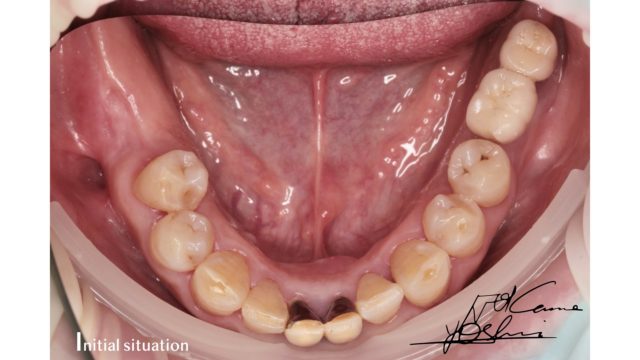

お口の下部、BEFORE写真です。